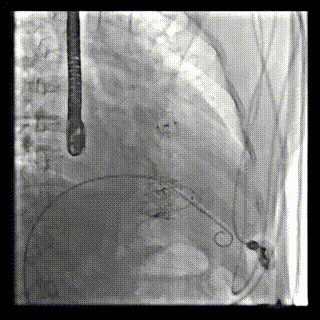

2021年12月24日,復(fù)旦大學(xué)附屬中山醫(yī)院葛均波院士團(tuán)隊(duì)成功應(yīng)用LuX-Valve Plus為一例極重度三尖瓣反流(TR)合并房顫、房缺的患者完成了經(jīng)血管三尖瓣置換術(shù),這是在前基礎(chǔ)上,本周完成的第三例經(jīng)血管三尖瓣置換手術(shù),葛均波院士、周達(dá)新教授等與心外科魏來教授、賴顥教授,心超室的潘翠珍教授、李偉教授及麻醉科的郭克芳教授共同完成了本周手術(shù),均獲得圓滿成功!患者術(shù)后超聲顯示無TR,臨床癥狀明顯改善。本周手術(shù)的成功也為L(zhǎng)uX-Valve Plus救治性臨床研究添上了濃墨重彩的一筆。

本周三例接受LuX-Valve Plus經(jīng)血管三尖瓣置換術(shù)的患者中,第一例患者為冠狀動(dòng)脈旁路移植術(shù)+Bentall+二尖瓣成形術(shù)后;第二例患者為永久起搏器植入術(shù)后,存在跨三尖瓣導(dǎo)線;第三例患者合并房顫、房缺及左心耳封堵術(shù)后。

三例患者入院后,葛均波院士團(tuán)隊(duì)周達(dá)新教授、潘文志教授、張?jiān)床┦俊㈥惿┦考靶某业呐舜湔浣淌?、李偉教授?duì)患者的情況進(jìn)行詳細(xì)評(píng)估和討論,最終決定為三例患者選擇LuX-Valve Plus40mm、50mm和50mm型號(hào)的瓣膜進(jìn)行手術(shù)治療。手術(shù)后即刻拔除氣管插管,術(shù)后患者三尖瓣反流癥狀得到顯著改善,復(fù)查心超結(jié)果顯示人工三尖瓣瓣膜支架固定穩(wěn)定,瓣葉關(guān)閉形態(tài)未見異常,未見明顯反流。